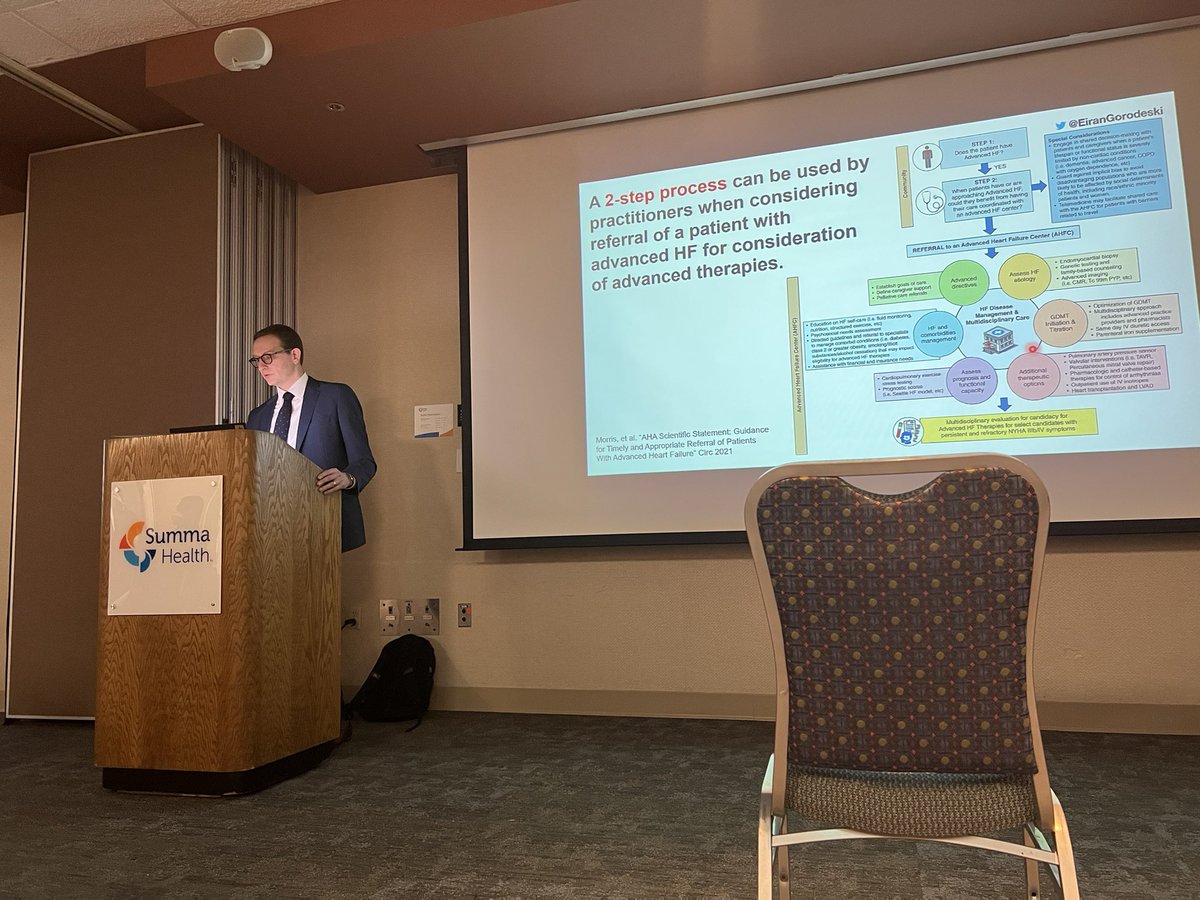

It was so awesome to finally have a guest speaker for grand rounds! Eiran Gorodeski, MD, MPH gave us a fantastic lecture on heart failure care in 2021 here at Summa Health.